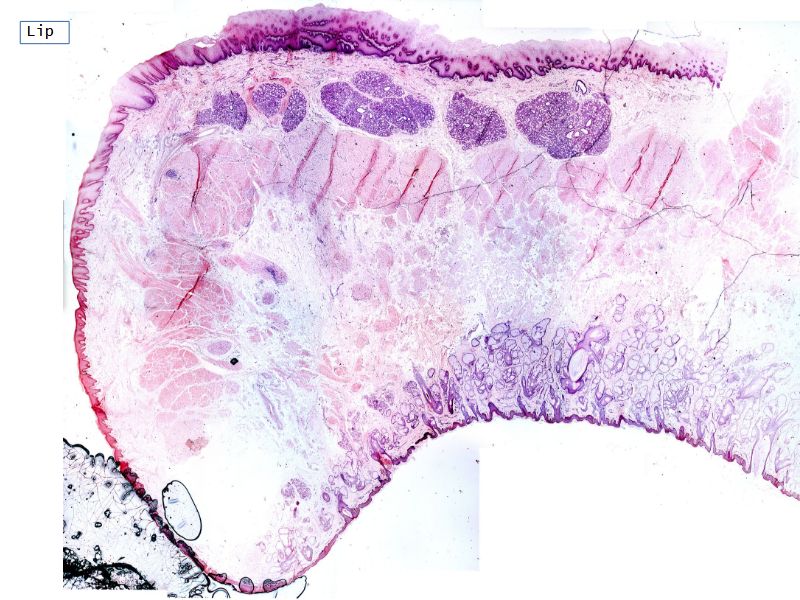

Fill in all the missing labels, and assess as you move through the slides. Answers on the down slide. It is important to do this using pen and paper, and not just glance through the images.